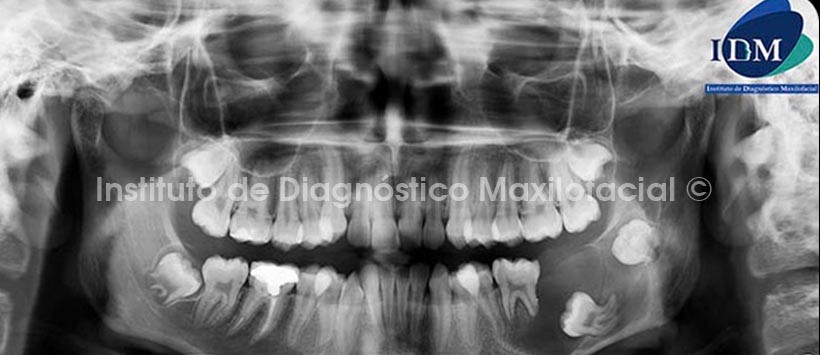

A la evaluación de la radiografía panorámica se observa una imagen radiolúcida de límites definidos y bordes corticalizados, localizada en el cuerpo y rama mandibular del lado izquierdo, que condiciona la reabsorción radicular de la pieza 36, el desploazamiento caudal de la pieza 37 y distal de la 38. Así mismo, se evidencia el adelgazamiento del reborde basal y el desplazamiento caudal del conducto dentario inferior (Fig 1).